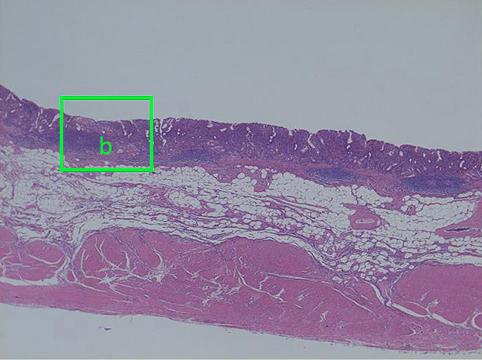

疾病(病理主体)的分类恶性上皮性肿瘤/腺癌

检查方法病理切片(微观)

肿瘤的肉眼分类0型(表在型)/IIb型(IIb+IIa)

肿瘤最大直径40以上

肿瘤的深度m